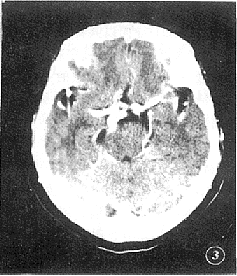

图3 与图2同一病例,较图2上一层面,见迂曲延长的基底动脉达鞍上池层面

讨论:基底动脉延长扩张症,是指该动脉过度延长与扩张,其最常见的病因为高血压脑动脉硬化所致,发病年龄在50~70岁。虽然病变的动脉不易破裂,但因其扩张而使脑干缺血或受压而产生基底动脉供血不足和颅神经功能障碍等临床表现。本病临床误诊率高,而CT检查是诊断该疾病最安全、有效的手段,尤其是增强加薄层扫描,确诊率高。可避免单纯平扫因岩锥骨伪影造成的漏诊。本病CT诊断的标准是凡基底动脉超出斜坡或鞍背的范围,或基底动脉分叉点超出了鞍上池层面,即可诊断为过度延长,基底动脉直径大于4.5 mm,即可诊断为扩张。, 百拇医药